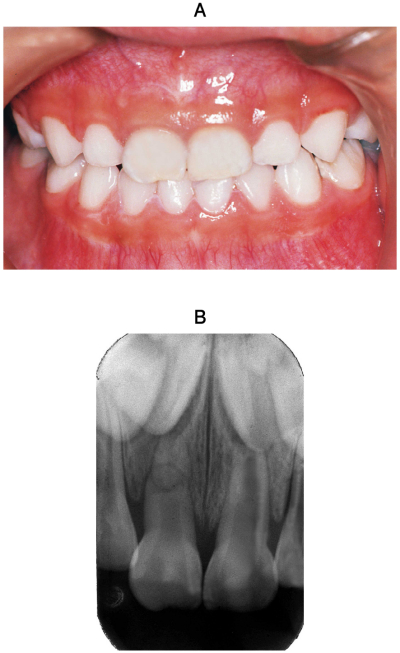

5歳の女児。上顎右側乳中切歯の外傷を主訴として来院した。昨日、転倒し、A⏌を打撲したが、自発痛が軽度であったため、そのままにしていたという。A⏌の動揺度は度で打診痛を認める。初診時の口腔内写真とエックス線写真を示す。

適切な対応はどれか。1つ選べ。